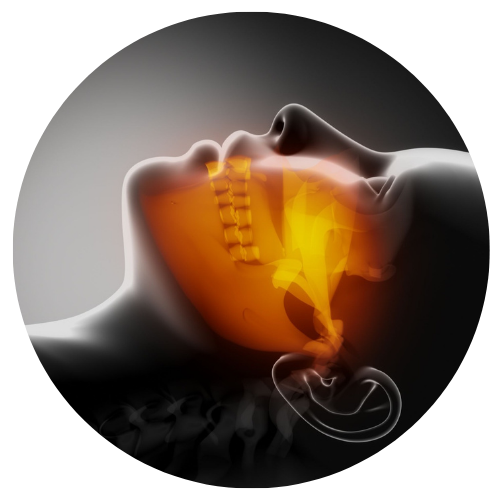

Um dos principais benéficos de pacientes submetidos a cirurgia ortognática é a melhora da função respiratória; Pacientes diagnosticados com apneia obstrutiva do sono apresentam melhora considerável após a realização deste procedimento cirúrgico.